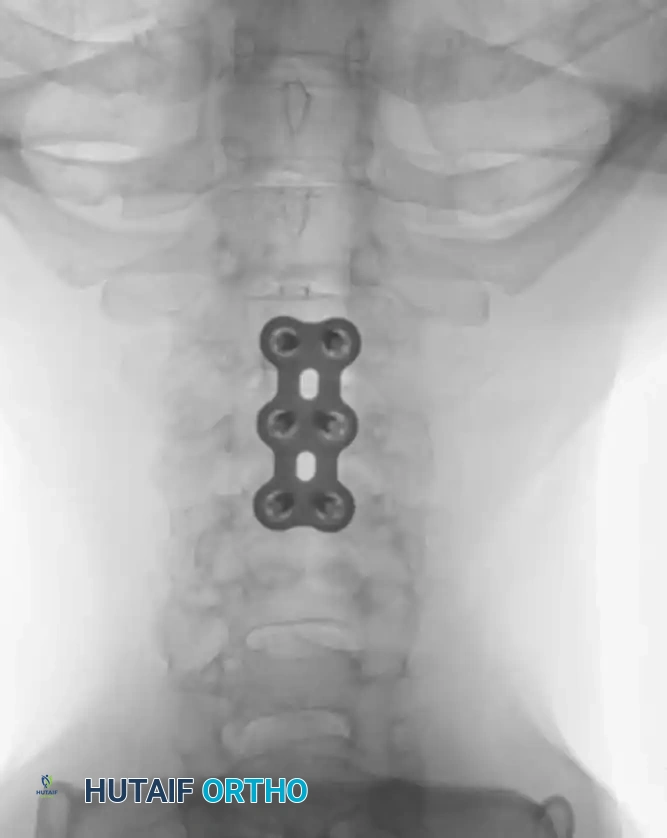

Anterior Plating Technique (Technique 35-16)

When anterior column reconstruction is required (e.g., post-corpectomy), anterior plating provides rigid stabilization.

- Measurement and Selection: Measure the distance between the middle of the cranial vertebra and the middle of the caudal vertebra to be included in the fixation. Use this caliper measurement to select the appropriate plate length.

- Contouring: If necessary, use a plate bender to conform the plate to the patient's specific spinal anatomy. Make several slight bends along the length of the plate and between the screw holes to obtain a consistent radius of curvature.

- Positioning: Using a plate holder, place the plate on the vertebral column in the optimal anatomical position.

- Temporary Fixation: Temporarily fix the plate with small pins screwed into the cortical wall. Insert these self-cutting pins diagonally through the screw holes to obtain sufficient provisional stability.

- Drilling: Place the drill guide on the plate. The guide limits pilot holes to the orientation of the integrated blocking ring (0 to ± 10 degrees sagittally and 6 degrees axially). Use the appropriate drill bit (10 mm, 12 mm, 14 mm, 16 mm, or 18 mm) to prepare the pilot hole.

- Screw Insertion: While tapping is an option, modern screws are typically self-tapping. Insert the 4.0-mm or 4.5-mm screws into the pilot holes. Tighten until locked into the plate, ensuring the locking mechanism (washer) fully covers the screw head.

- Graft Securing: If a corpectomy and structural grafting were performed, secure the graft to the plate using standard 4-mm screws placed in the intermediary screw holes.

- Closure: Thoroughly irrigate the wound and close in layers over a subfascial drain.

Associated Surgical & Radiographic Imaging